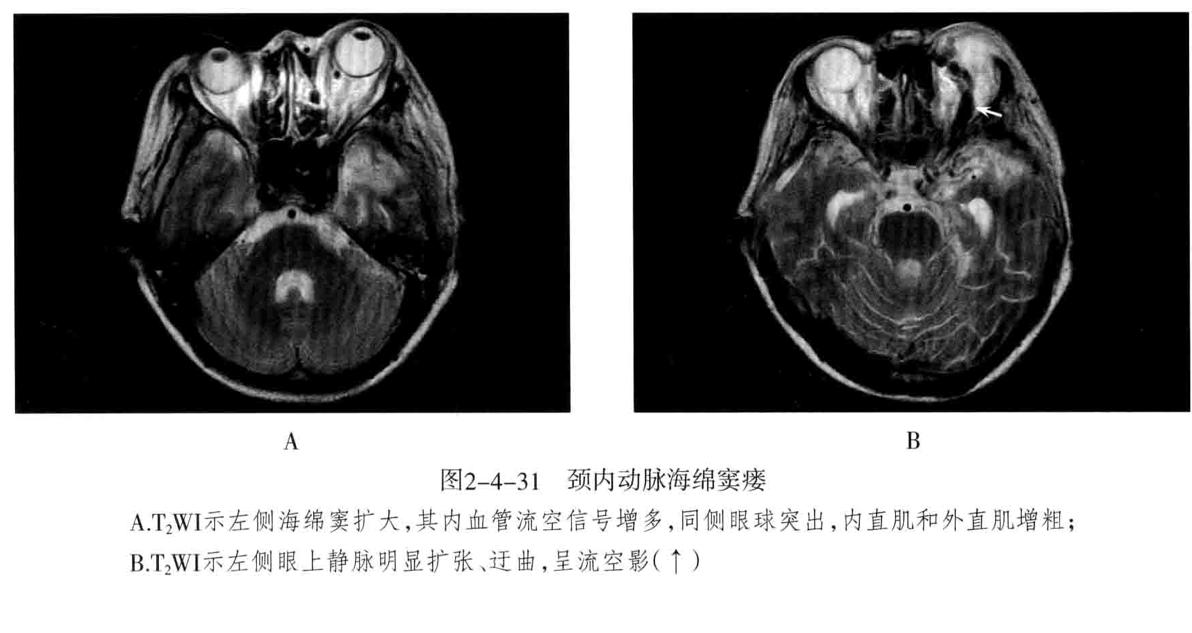

颈内动脉海绵窦瘘: 定义:指海绵窦段的颈内动脉及其分支破裂,与海绵窦之间形成动静脉的异常沟通所引起的一组神经眼科综合征。75%以上由外伤性引起,多为单侧发病,眼部征像多出现在患侧。

- CT表现为海绵窦增宽,增强扫描海绵窦明显强化,眼上静脉增粗扭曲。CTA可清楚显示扩张的眼上静脉和海绵窦。眼外肌充血增粗和眼球突出。

- MRI:海绵窦扩大,海绵窦内血管影增多,且迂曲、粗大、不规则。同侧眼上静脉明显扩张,呈迂曲的流空信号。眼外肌增粗充血和眼球突出。需与海绵窦肿瘤性病变鉴别。